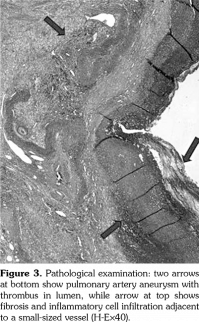

Pathergy test was performed due to the presence of recurrent oral and genital ulcers, supporting the diagnosis of BD. Pathergy test was positive and he was diagnosed as BD according to the history, physical examination and laboratory findings. Monthly intravenous cyclophosphamide pulses combined with high dose methyl-prednisone were initiated and followed by prednisolone 2 mg/kg/day. Afterwards, left lower lobectomy was performed. Pathological examination revealed PAA with thrombus in the lumen, fibrosis and lymphoplasmacytic inflammatory cell infiltration adjacent to small- and medium- sized vessels (Figure 3). He was clinically well after lobectomy and admitted for the second pulse immunosuppressive therapy. Meanwhile, CT angiography was performed to evaluate the aneurysm at the right lower lobe which showed regression of PAA from 16 mm to 6 mm in diameter. Endovascular embolization was planned for the right lower lobe PAA. However, unfortunately, he presented with massive hemoptysis five days later. The patient passed away with massive hemoptysis originating from the right lower lobe PAA.